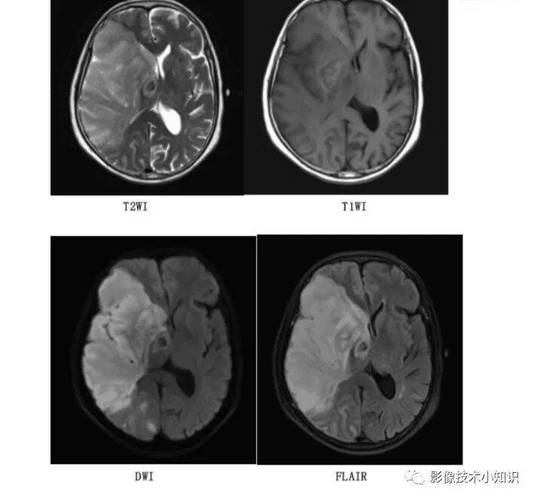

- 关键序列:弥散加权成像

- 这是发现早期脑梗死的“王牌”序列!

- 原理: DWI主要探测的是水分子的布朗运动,在急性脑梗死早期,细胞毒性水肿导致细胞内水分子增多,且这些水分子被限制在缩小的细胞空间内,运动受到限制(即“水分子扩散受限”)。

- 表现: 在DWI图像上,这种“水分子扩散受限”的区域会显示为明显的高信号(亮白色),这个改变在脑缺血发生后的几分钟内就可能开始出现,并且在发病后30分钟到1小时内,诊断的敏感性和特异性就非常高了。

- 表观弥散系数: 与DWI配对使用,可以帮助确认DWI上的高信号是真的梗死,还是其他伪影,真正的梗死在ADC图上会显示为低信号(暗黑色)。

- 液体衰减反转恢复: 对水肿非常敏感,在早期也能看到梗死区域呈高信号,但不如DWI特异,因为它也会受其他病变(如炎症、肿瘤)影响。